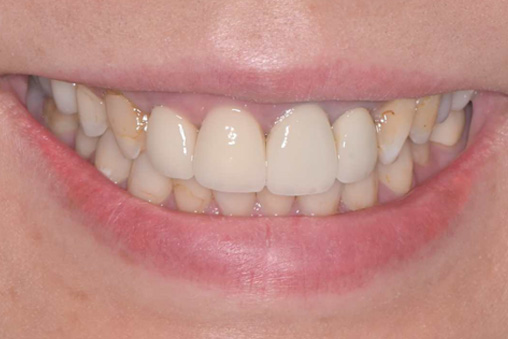

- 短期集中治療による治療例 海外在住 滞在期間 1週間

-

治療本数:11本

治療回数:2回

(審美治療が主訴、歯のホワイトニングも行いました)■治療前(顔貌)

↓ ■治療前(口腔内)

↓ ■治療後(顔貌)

■治療後(口腔内)